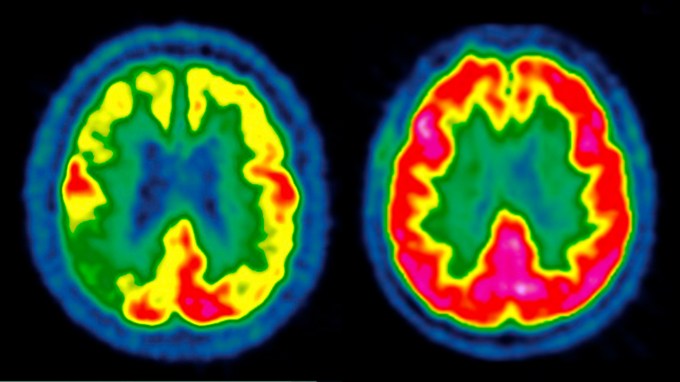

GLP-1 drugs failed to slow Alzheimer’s in two big clinical trials

Tantalizing results from small trials and anecdotes raised hopes that drugs like Ozempic could help. Despite setbacks, researchers aren’t giving up yet.